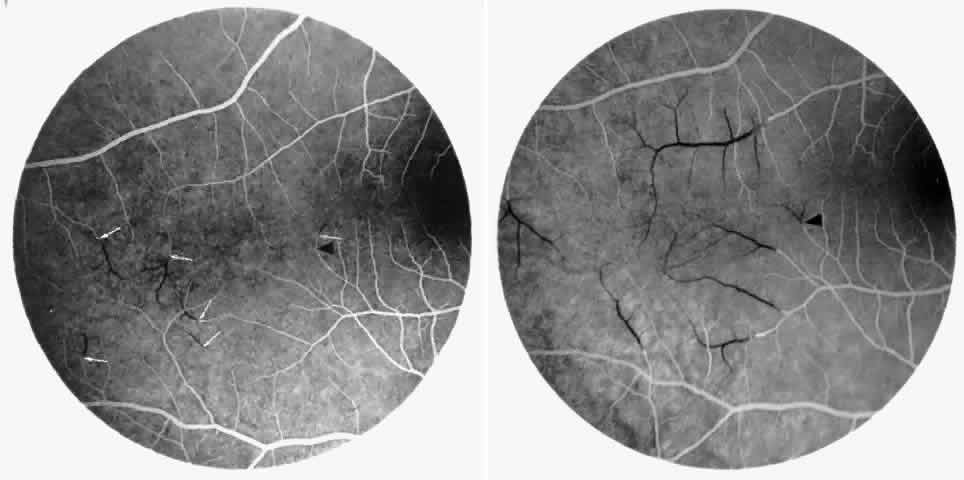

The occluded arterioles may be invisible or may have a “silver-wire” or chalk-white appearance, as first described by Goodman and colleagues39 (Fig. 21). Fluorescein angiography may demonstrate an abrupt complete occlusion at the interface between peripheral nonperfused and posterior perfused retina. Frequently, this occlusion will take place just distal to a branching vessel, giving the appearance of a freshly pruned rose bush. The nonperfused anterior peripheral retina will have a grayish brown appearance and on fluorescein angiography will appear blurred without clearly defined fundus markings.

STAGE II: PERIPHERAL ARTERIOLAR-VENULAR ANASTOMOSES. Following occlusion of the terminal arterioles, anastomotic channels form to channel the blood from the occluded arteriole to the nearest venules. These anastomoses form at the interface between the perfused and nonperfused retina. Most likely, they are dilated preexisting capillaries rather than new vessels, since they do not leak on fluorescein angiography. The redirection of blood flow is probably due to hydrostatic forces (Figs. 22 and 23).

|